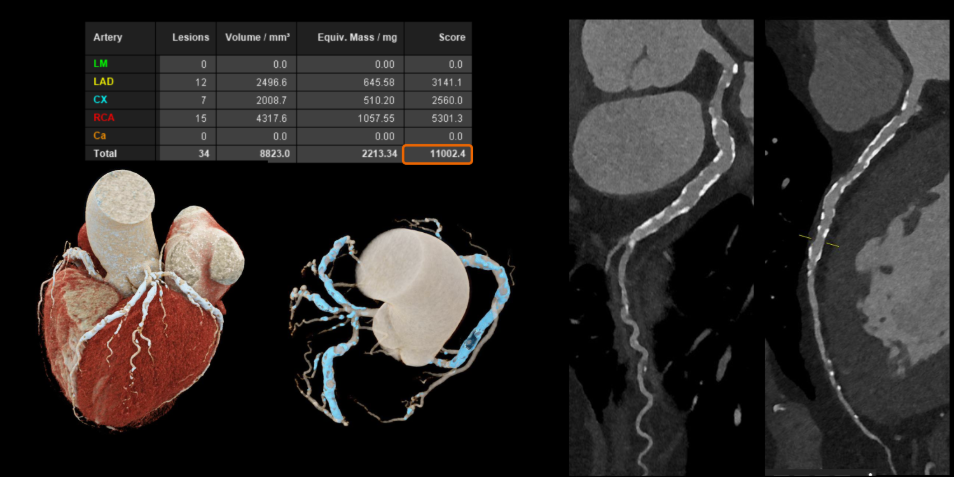

Với các bệnh tim mạch, đặc biệt ở những bệnh nhân đã đặt stent hoặc có mạch vành bị vôi hóa nặng – vốn là những trường hợp khó đánh giá bằng CT thông thường. Công nghệ này cho phép hình ảnh rõ ràng hơn đáng kể. Nhờ đó, bác sĩ có thể quan sát chính xác lòng mạch và các mảng xơ vữa, ngay cả khi bệnh nhân có nhịp tim cao hoặc loạn nhịp mà không cần sử dụng thêm thuốc hỗ trợ.

Công nghệ cắt lớp vi tính lượng tử: Mở ra cơ hội phát hiện sớm và điều trị chính xác hơn cho người bệnh- Ảnh 2.

Hình ảnh mạch vành cho thấy độ rõ cao hơn, giảm nhiễu và giúp đánh giá chính xác hơn (Nguồn: Siemens Healthineers)